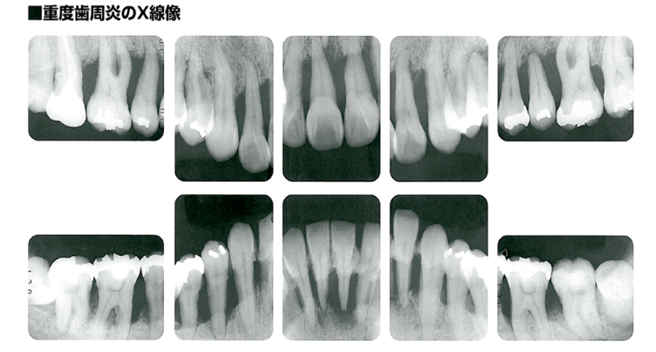

4.重度に侵攻した歯周病(歯周炎)

歯周病が重度に進行して歯槽骨が無くなり保存できず抜歯された歯